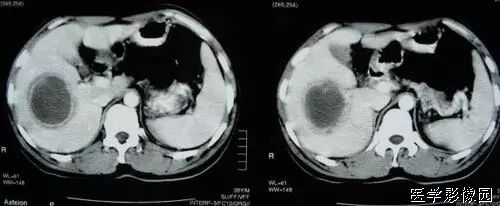

系统性红斑狼疮

2、靶征(肠壁)

主要见于腹部增强扫描,增后的肠壁表现为三层结构,内层和外层是高密度强化层,两者之间是低密度的中间层。

靶征出现于可导致长鼻粘膜水肿、炎症或两者同时存在的多种肠管病变。其内层代表粘膜层,外层代表固有层和浆膜层,由于对比剂的强化而成高密度,中层的低密度被认为是由于粘膜下层水肿所致。靶征的出现提示粘膜和固有层、浆膜层的充血并伴有粘膜下水肿和炎症。颈静脉注射对比剂后,各层之间的密度差异在动脉早期和门晚期表现最为清楚,如果对比剂注入速度太慢、剂量太少以及延时超过2分钟,此征根本不出现。但是当粘膜下水肿非常严重时,CT平扫也可能出现。如果肠管内充满水而使肠管扩张时,靶征显示更为清楚。

CT扫描时,良性的肠管病变通常表现为肠壁的环形均匀性增厚,厚度从粘膜面到浆膜面一般不超过1公分,根据病因和病变严重程度的不同,偶尔可能超过1公分,但一般在2公分以内。肠壁出现靶征的病变主要见于缺血性肠病、小肠壁内出血、克隆氏病、溃疡性结肠炎、血管性疾病、感染性疾病、放射疾病和门脉高压所致肠粘膜水肿等。靶征并不是一个特异征象,但是在恶性病变中一般不出现此征,只是浸润性直肠癌是一个例外。

所以,一般情况下,靶征的出现,首先要考虑的是肠道的炎症性病变。

以下是空谷幽兰斑竹曾经发过的一个帖子,靶征非常典型: